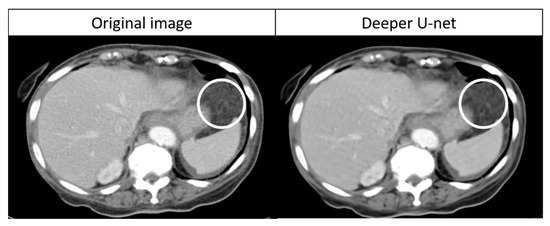

The detectability of abnormal lesions with deeper U-net was significantly better than that with RED-CNN: 95.2% (118/124) vs. 62.9% (78/124) (p < 0.0001) for reader 1 and 97.6% (121/124) vs. 36.3% (45/124) (p < 0.0001) for reader 2. The number of FN with deeper U-net were six and three for readers 1 and 2, respectively. All these abnormal lesions were non-measurable peritoneal dissemination, which were identified as slight subtle soft-tissue infiltration and reticulonodular lesions on the original CT image. The representative images of the FN case are shown in Figure 6.

Figure 6.

A representative undiagnosable lesion on denoised CT image with deeper U-net. Note: The circle shows non-measurable peritoneal dissemination. With deeper U-net, the score was 1 point for reader 1 and 2 points for reader 2.